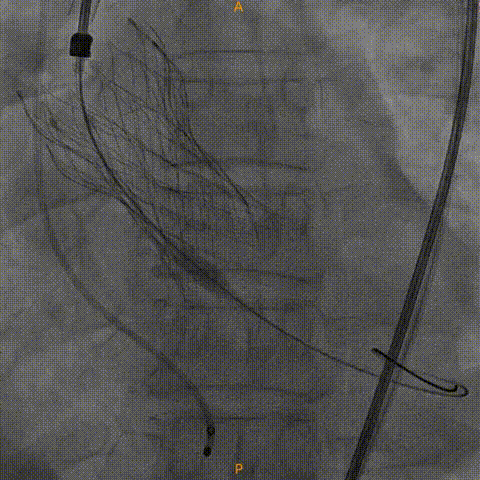

瓣膜零位定位释放

工作位造影

瓣膜完全释放

瓣膜膨胀不良进行球囊后扩

造影显示有瓣周漏

植入瓣中瓣

瓣中瓣形态良好,无反流